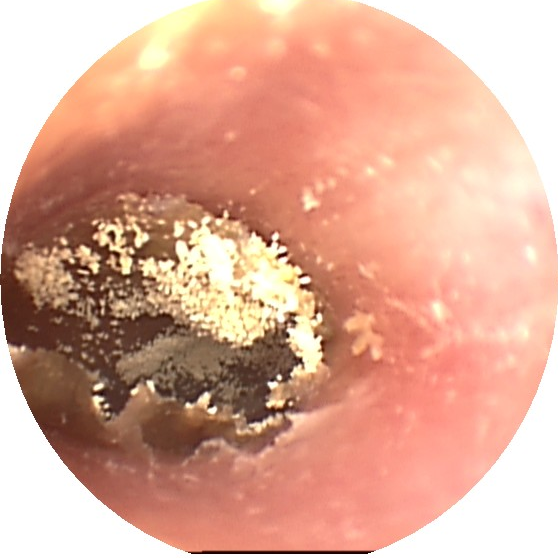

3、真菌性外耳炎

以曲霉菌、青霉菌及念珠菌为主的常见真菌侵入人的外耳道,引起外耳道真菌病。

症状和体征

多数可有耳痒,耳闷,部分可有耳鸣、听力下降。合并感染时可引起外耳道肿胀、疼痛和流脓。

治疗

及时至医院就诊,清除外耳道内真菌痂皮和分泌物。外耳道表面涂上抗真菌药物。同时也可用制霉菌素喷于外耳道。尽量保持外耳道干燥。